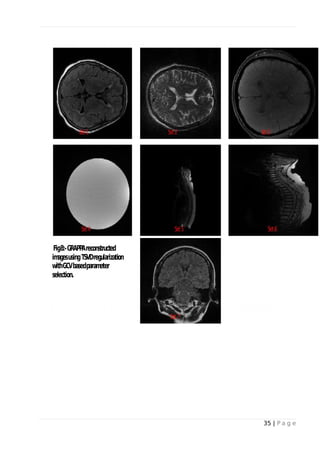

 L-curve method for selecting truncation parameter in TSVD:

Fig-1 and Fig-5 shows the plots of solution norm versus residual norm for data sets I to VII. The

circles indicate values of regularization parameter at each point on the L-curve. The optimum

parameter is at the corner of the L-curve. Dataset II and III shows sharp L-curve corner. Images

reconstructed using parameter chosen from L-curve corner are shown in Fig-2 and Fig-6.

Fig. 5: -L-Curve for TSVD regularization using GRAPPA with R=3.

Fig 6: - GRAPPA reconstructed images using TSVD regularization with L-Curve based

parameter selection.